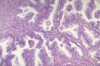

what do you notice about this prostate?

it is enlarged and has an increase in stroma and prostate glands

what kind of weight could you expect this hyperplasic prostate to be?

70 g

what is the pattern of increase in this fucked up prossy?

nodular (not uniform)

is the structure of this hyperplastic prostate maintained or not?

maintained

t is well-differentiated - there are too many glands but they resemble normal tissue